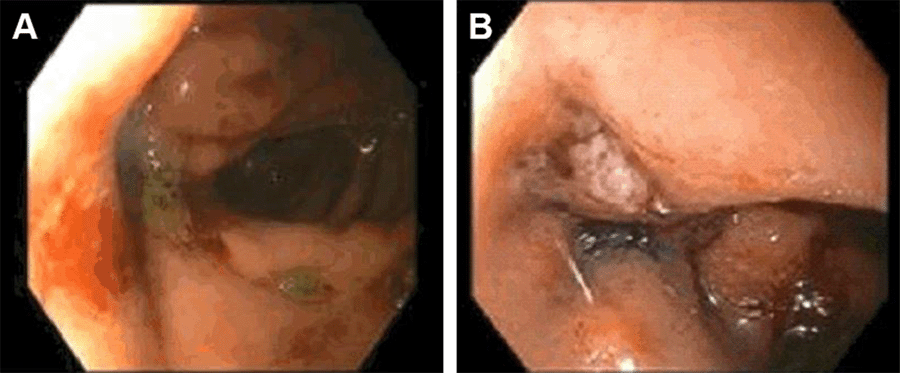

Endoscopy revealed a 1.2 cm fistula seen in the efferent limb just distal to the gastrojejunal anastomosis with clean margins (Figure 3A). After assessing the situation, the decision was made to close the fistula with endoscopic sutures and place covered metal stents in the afferent and efferent limbs under fluoroscopic guidance to exclude the fistula (Figure 3B).

Figure 3. Fistula Before (A) and After (B) Closure With Endoscopic Sutures. Published With Permission